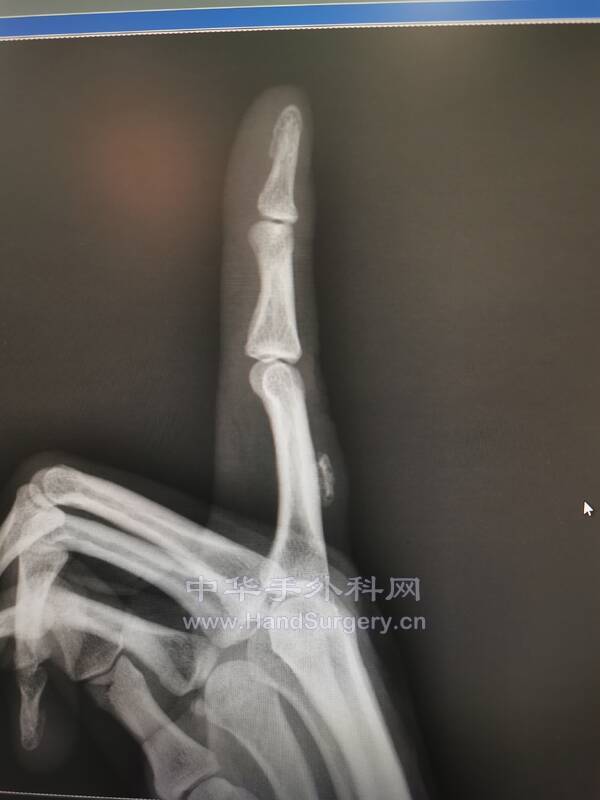

今天手术一个类似的病历

IMG_20210909_093659.jpg

IMG_20210909_093716.jpg

IMG_20210909_093842.jpg

在伸肌腱深处,指骨表面

和指骨结合不紧密

用骨剥轻轻一推就下来了

等待病理结果